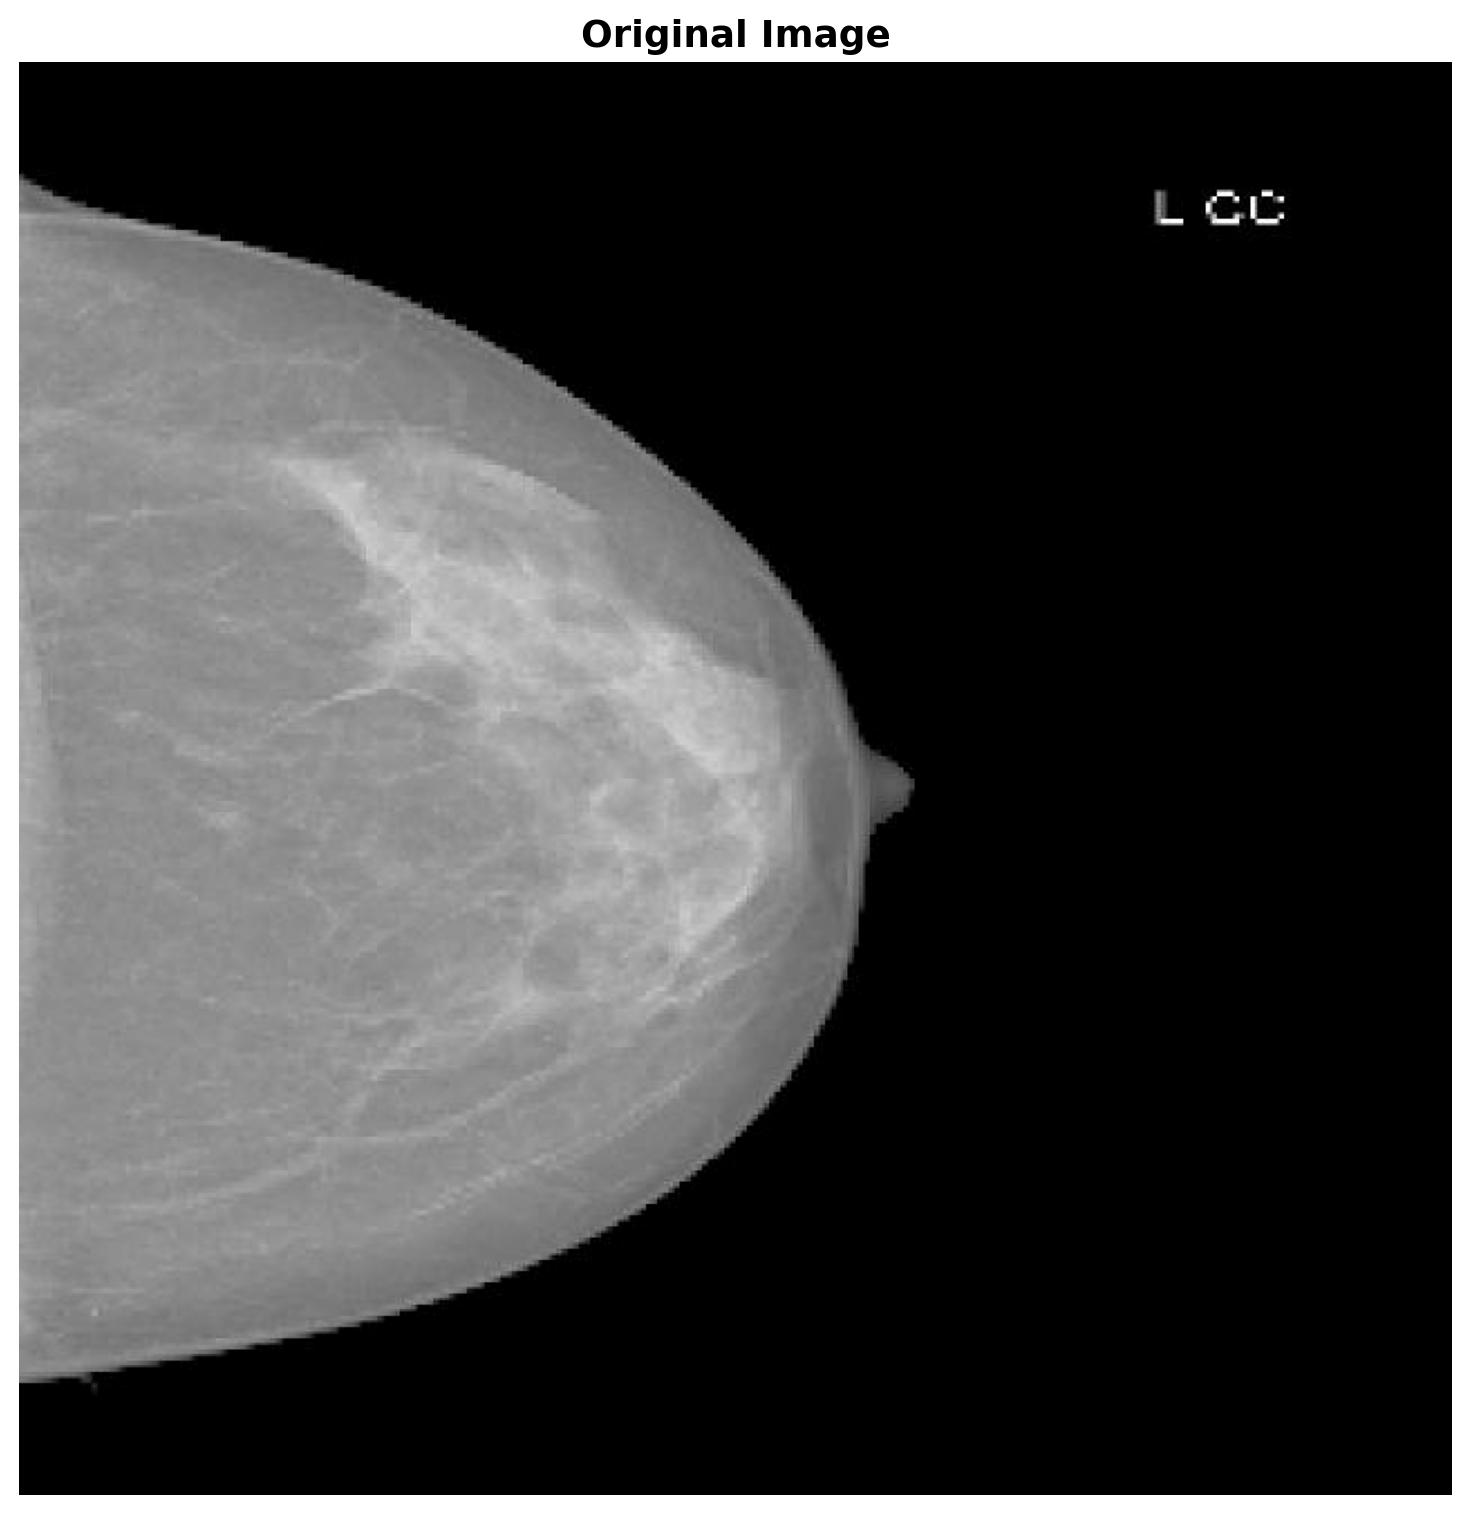

Let’s load the example image that we want to segment.

plt.title('Original Image', fontsize=14, fontweight='bold')

In what follows we run FCM with both distance metrics to compare their performance.